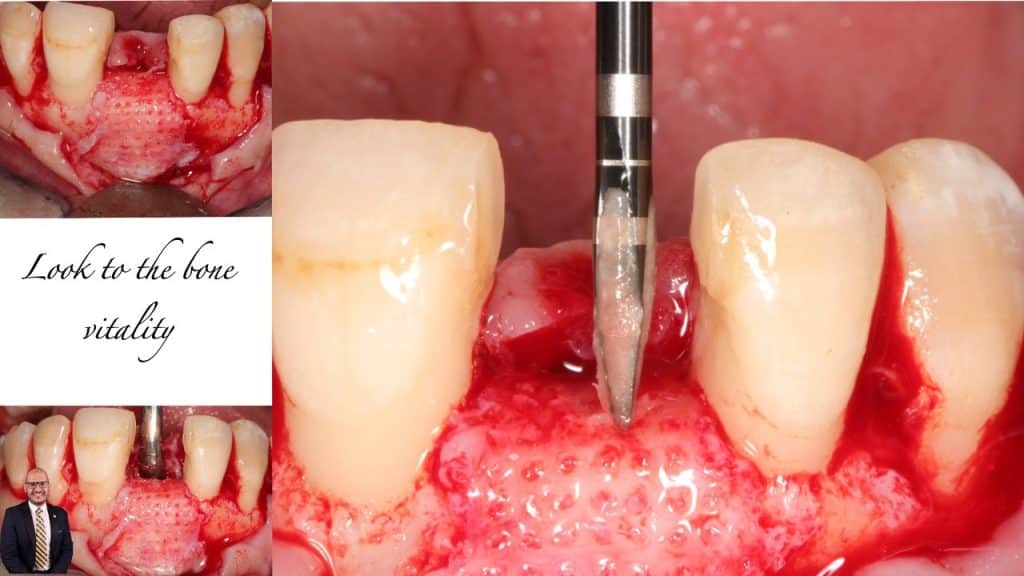

Type III socket patient, High risk esthetic case presented with hopeless #11, managed by staged approach to optimize patient’s expectations.